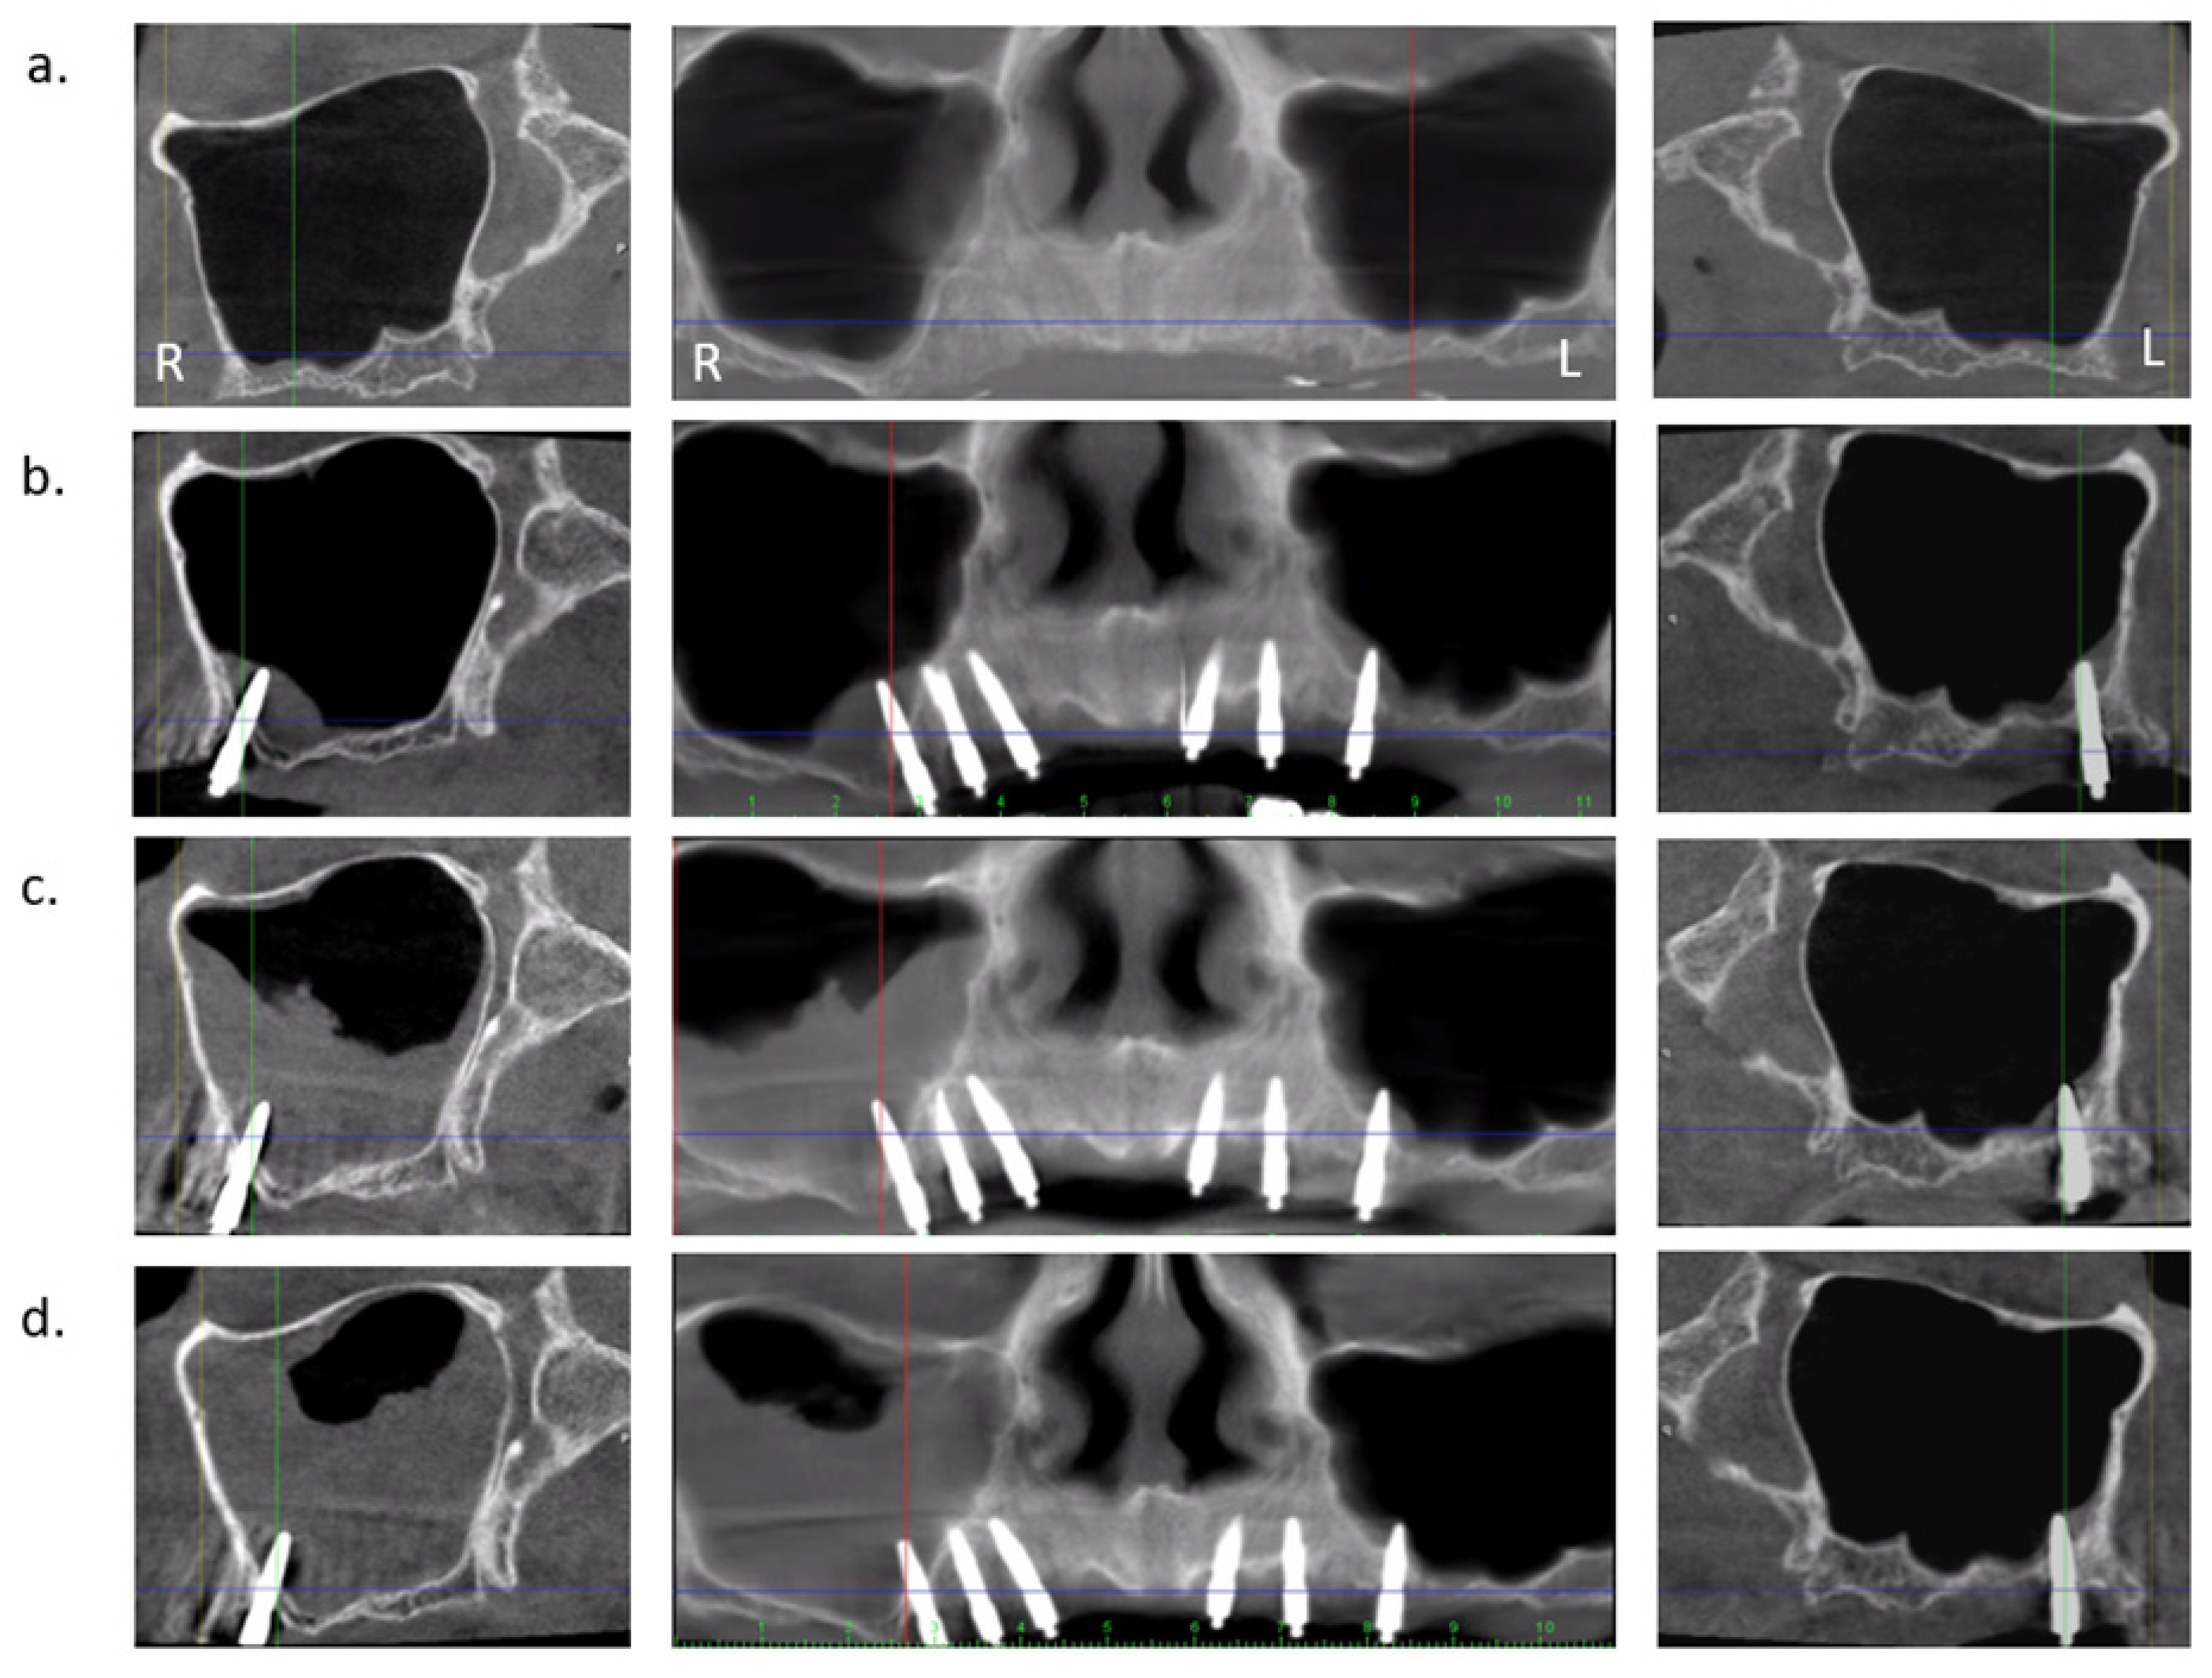

2.2. Radiological Examination

- Van Doorne, L.; Gholami, P.; D’Haese, J.; Hommez, G.; Meijer, G.; De Bruyn, H. Three-Dimensional Radiographic Outcome of Free-Handed Flaplessly Placed Mini Dental Implants in Edentulous Maxillae after 2-Years Function. J. Clin. Med. 2020, 9, 2120. [Google Scholar] [CrossRef] [PubMed]

- Janner, S.F.M.; Caversaccio, M.D.; Dubach, P.; Sendi, P.; Buser, D.; Bornstein, M.M. Characteristics and dimensions of the Schneiderian membrane: A radiographic analysis using cone beam computed tomography in patients referred for dental implant surgery in the posterior maxilla. Clin. Oral Implant. Res. 2011, 22, 1446–1453. [Google Scholar] [CrossRef]